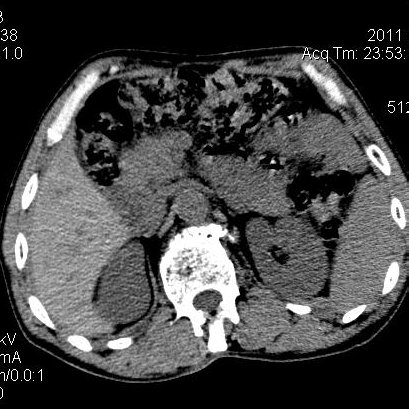

肝左叶发育异常

男性,55岁,骑摩托车摔倒后入院,自述右上腹疼痛

[backcolor=#FF0000]第一次诊断的时候也是这么肯定,可是床旁超声检查并没有发现明显异常,而且患者的一般症状都良好。还好临床只是保守治疗,没有立即手术,第二次复查的时候没有一点变化,又做了MRI检查,没有血肿,

这是一例肝左叶发育异常的,很个性吧~[/backcolor]